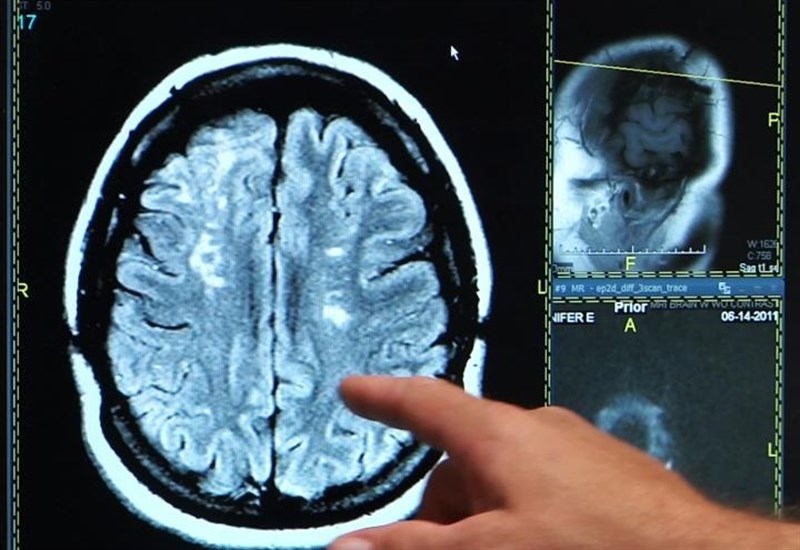

Destaca la administración que también han aumentado la cifra de pacientes tratados en la fase aguda con técnicas de revascularización. Así, el número de trombectomías mecánicas (extracciones de trombos alojados en las arterias cerebrales) registradas el pasado año fue de 122, 31 casos más que en el año 2015.

A esta cantidad es preciso sumar las fibrinólisis intravenosas, tratamientos para deshacer el trombo sin necesidad de intervención, que ascienden a unos 70 casos anuales.